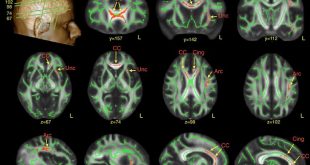

نوروسافاری| تصاویر اسکن مغزی مبتلایان به اتیسم تغییرات ظریفی را در مناطقی از مغز که دخیل در گفتار و شناسایی چهره می باشند، آشکار ساخت. · دانشمندان از مغز ۶۱ مرد مبتلا به اتیسم تصویر برداری کردند. · آنها ماده سفید مغز در این تصاویر را با مغز افراد …

نوروسافاری| قرار گرفتن در معرض ریزگردها و ذرات معلق تأثیری منفی در میزان ماده سفید در مغز بر جا خواهد گذاشت. به گزارش نوروسافاری به نقل از آنا، پژوهشگران آمریکایی دانشگاه کالیفرنیای جنوبی اعلام کردند در مغز افراد مسنی که در مناطق آلودهتر زندگی میکنند، ماده سفید کمتری یافتهاند. …

نوروسافاری| با توجه به تحقیق جدیدی که در دانشکده پزشکی پرلمن و دانشکده وارتون در دانشگاه پنسیلوانیا انجام شده است، افراد با سطح بالاتری از مهارت های استدلال اخلاقی، دارای ماده خاکستری بیشتری در مناطقی از مغز هستند که در رفتاهای اجتماعی پیچیده، تصمیم گیری و پردازش تعارضات نقش …